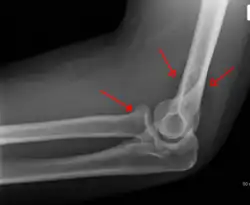

Fat pad sign

The fat pad sign, also known as the sail sign, is a potential finding on elbow radiography which suggests a fracture of one or more bones at the elbow. It may indicate an occult fracture that is not directly visible. Its name derives from the fact that it has the shape of a spinnaker (sail).[1] It is caused by displacement of the fat pad around the elbow joint. Both anterior and posterior fat pad signs exist, and both can be found on the same X-ray.

In children, a posterior fat pad sign suggests a condylar fracture of the humerus. In adults it suggests a radial head fracture.

The fat pad sign is invaluable in assessing for the presence of an intra-articular fracture of the elbow. An anterior fat pad is often normal. However a posterior fat pad seen on a lateral x-ray of the elbow is always abnormal. The patient will be unable to flex their elbow and requires orthopaedic input.[2]